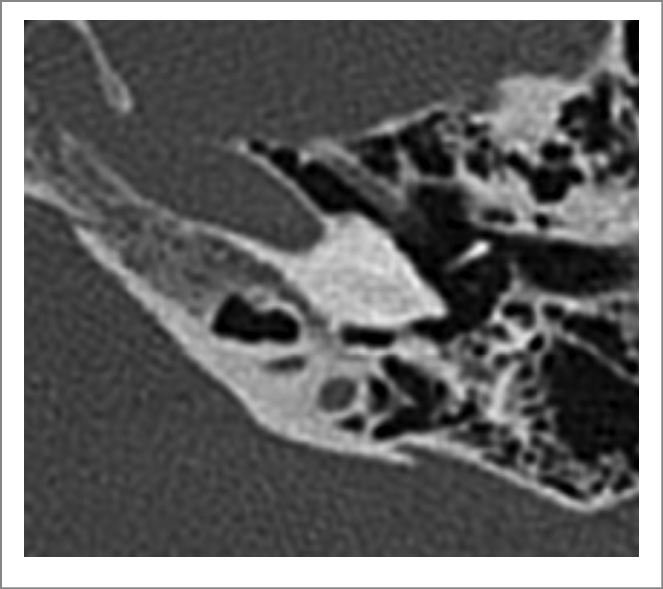

На КТ ВК от 27.03.2022 выявлены КТ-признаки субтотальной оссификации структур лабиринта, СКУ справа частично проходим (рис. 1, 2).

Рис. 1. КТ-картина правой ВК перед операцией.

Рис. 2. КТ-картина левой ВК перед операцией.